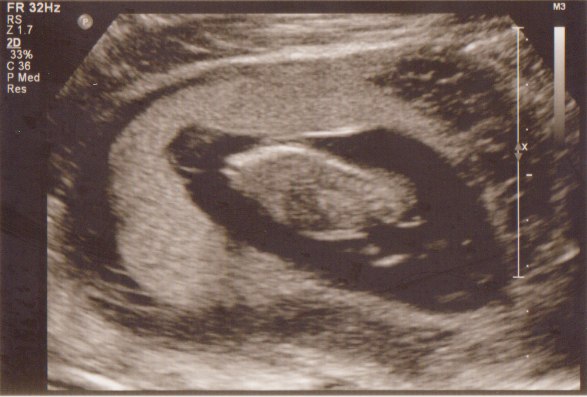

men det er da stadig til, at overkomme, hehe. Nu venter jeg bare på svare, for med størrelse forskelle og det er tvillinger, kan der jo være problemer med en scanning lige nu og her.